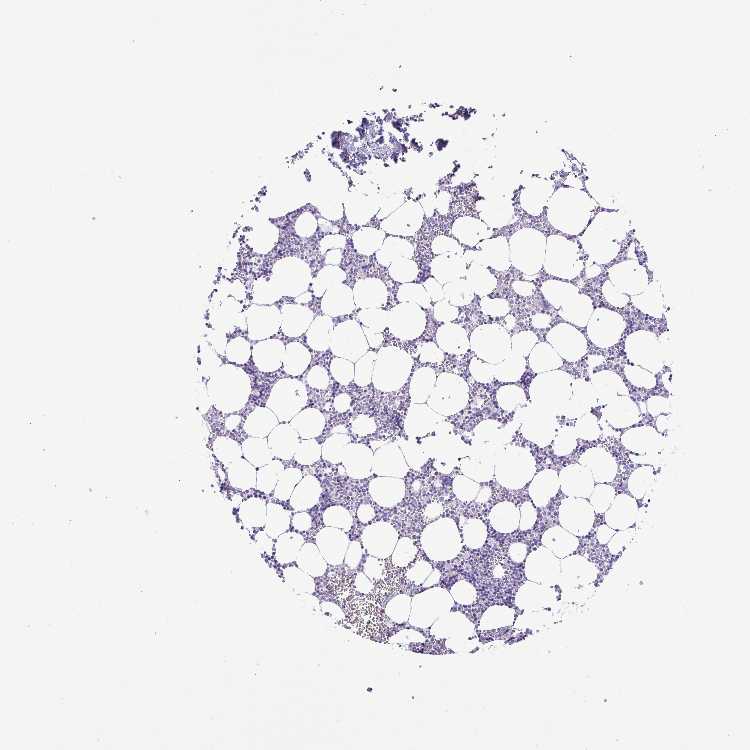

BONE MARROW - Antibody stainingi

Antibody staining in the annotated cell types in the current human tissue is reported as not detected, low, medium, or high, based on conventional immunohistochemistry profiling in selected tissues. This score is based on the combination of the staining intensity and fraction of stained cells.

Each image is clickable and will lead to virtual microscopy that enables deeper exploration of all samples and also displays staining intensity scores, fraction scores and subcellular localization as well as patient and tissue information for each sample.

Antibody HPA051880

Hematopoietic cells Not detected